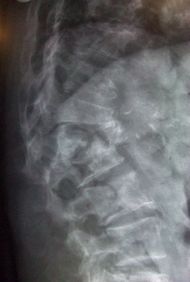

Multiple osteoporotic wedge fractures demonstrated on a lateral thoraco-lumbar

قد تبدأ الأعراض بصورة مفاجئة أو حادة; على هيئة آلام بالظهر, وعادة ما يكون ذلك نتيجة لحدوث كسر في إحدى فقرات العمود الفقري, لكن الأكثر شيوعا هو حدوث أعراض المرض بصورة تدريجية, وقد يكتشف الطبيب لدى الفحص الروتيني للمرضى المتقدمين في السن وجود كسور بسيطة بالفقرات, وقد لا تؤدي تلك الكسور إلى أية مضاعفات مثل الضغط على أعصاب الحبل الشوكي. وقد تقتصر شكوى المريض على الانحناء المتزايد لقامته نتيجة لانخفاض كثافة عظام الفقرات ونقص كتلتها.

- كسور العمود الفقري: 44%.